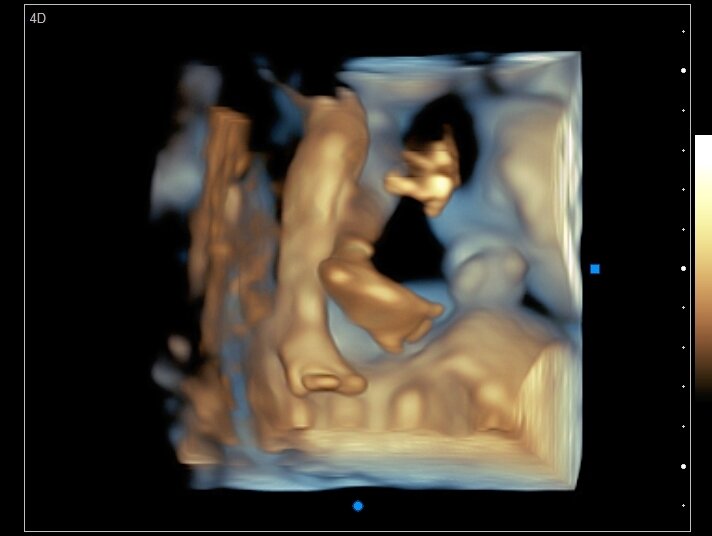

3D images are used to show you three-dimensional external images, great for taking a look at babies facial features. These can be used at any stage of pregnancy. To see great facial detail we recommend 26-35 weeks of pregnancy.

3D images are used to show you three-dimensional external images, great for taking a look at babies facial features. These can be used at any stage of pregnancy. To see great facial detail we recommend 26-35 weeks of pregnancy.